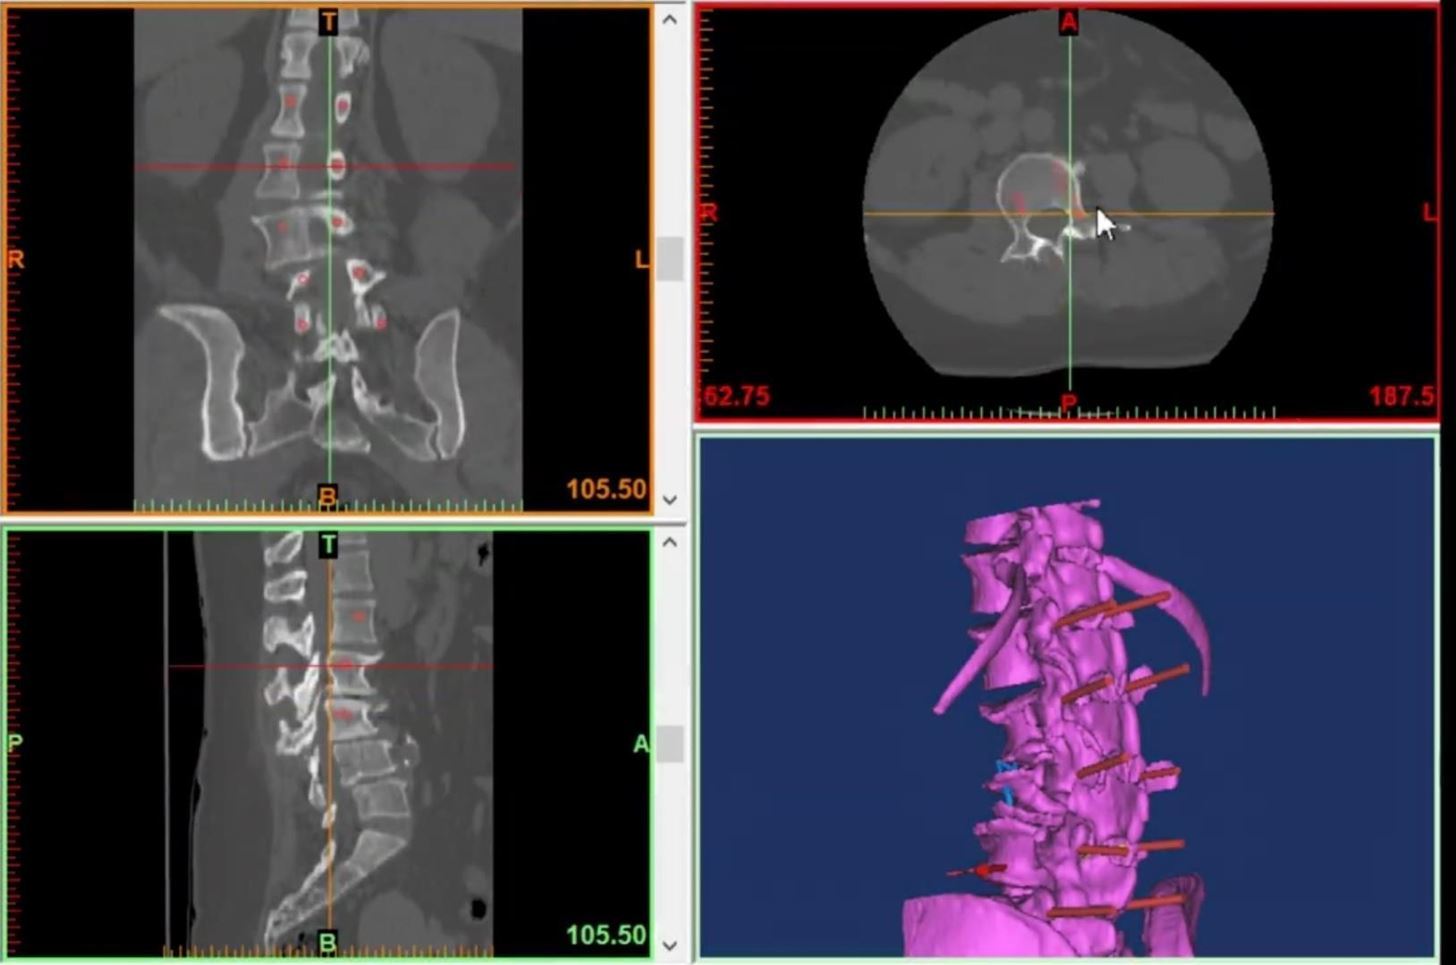

除此之外,巴西圣卡塔琳娜州的一名骨科医生Henrique Lampert也在使用HoloLens构建可视化椎骨模型,帮助他以安全和相对低廉的价格来提高手术质量;

医生用Hololens简化骨髓手术